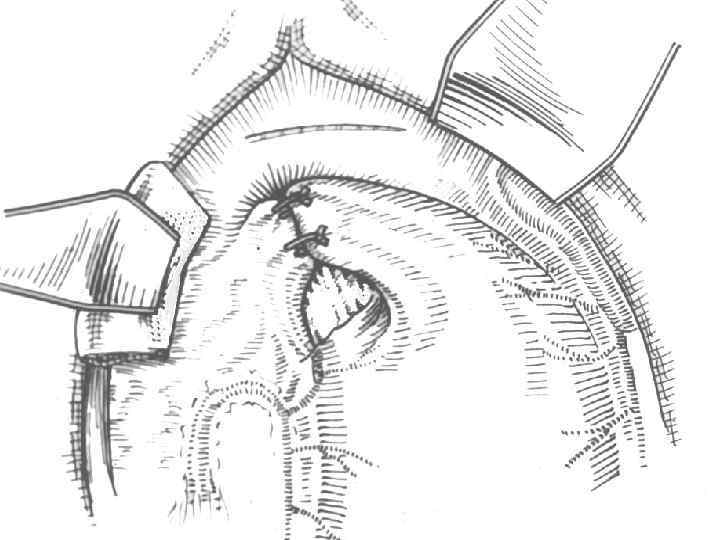

Хирургическое лечение синдрома приводящей петли и порочного круга

Виды оперативных вмешательств при синдроме приводящей петли: • Реконструкция по Ру-Опокину • Перевод резекции желудка из Бильрот-II в • • Бильрот-I Энтеро-энтероанастомоз по Брауну; Подшивание приводящей петли к малой кривизне желудка;